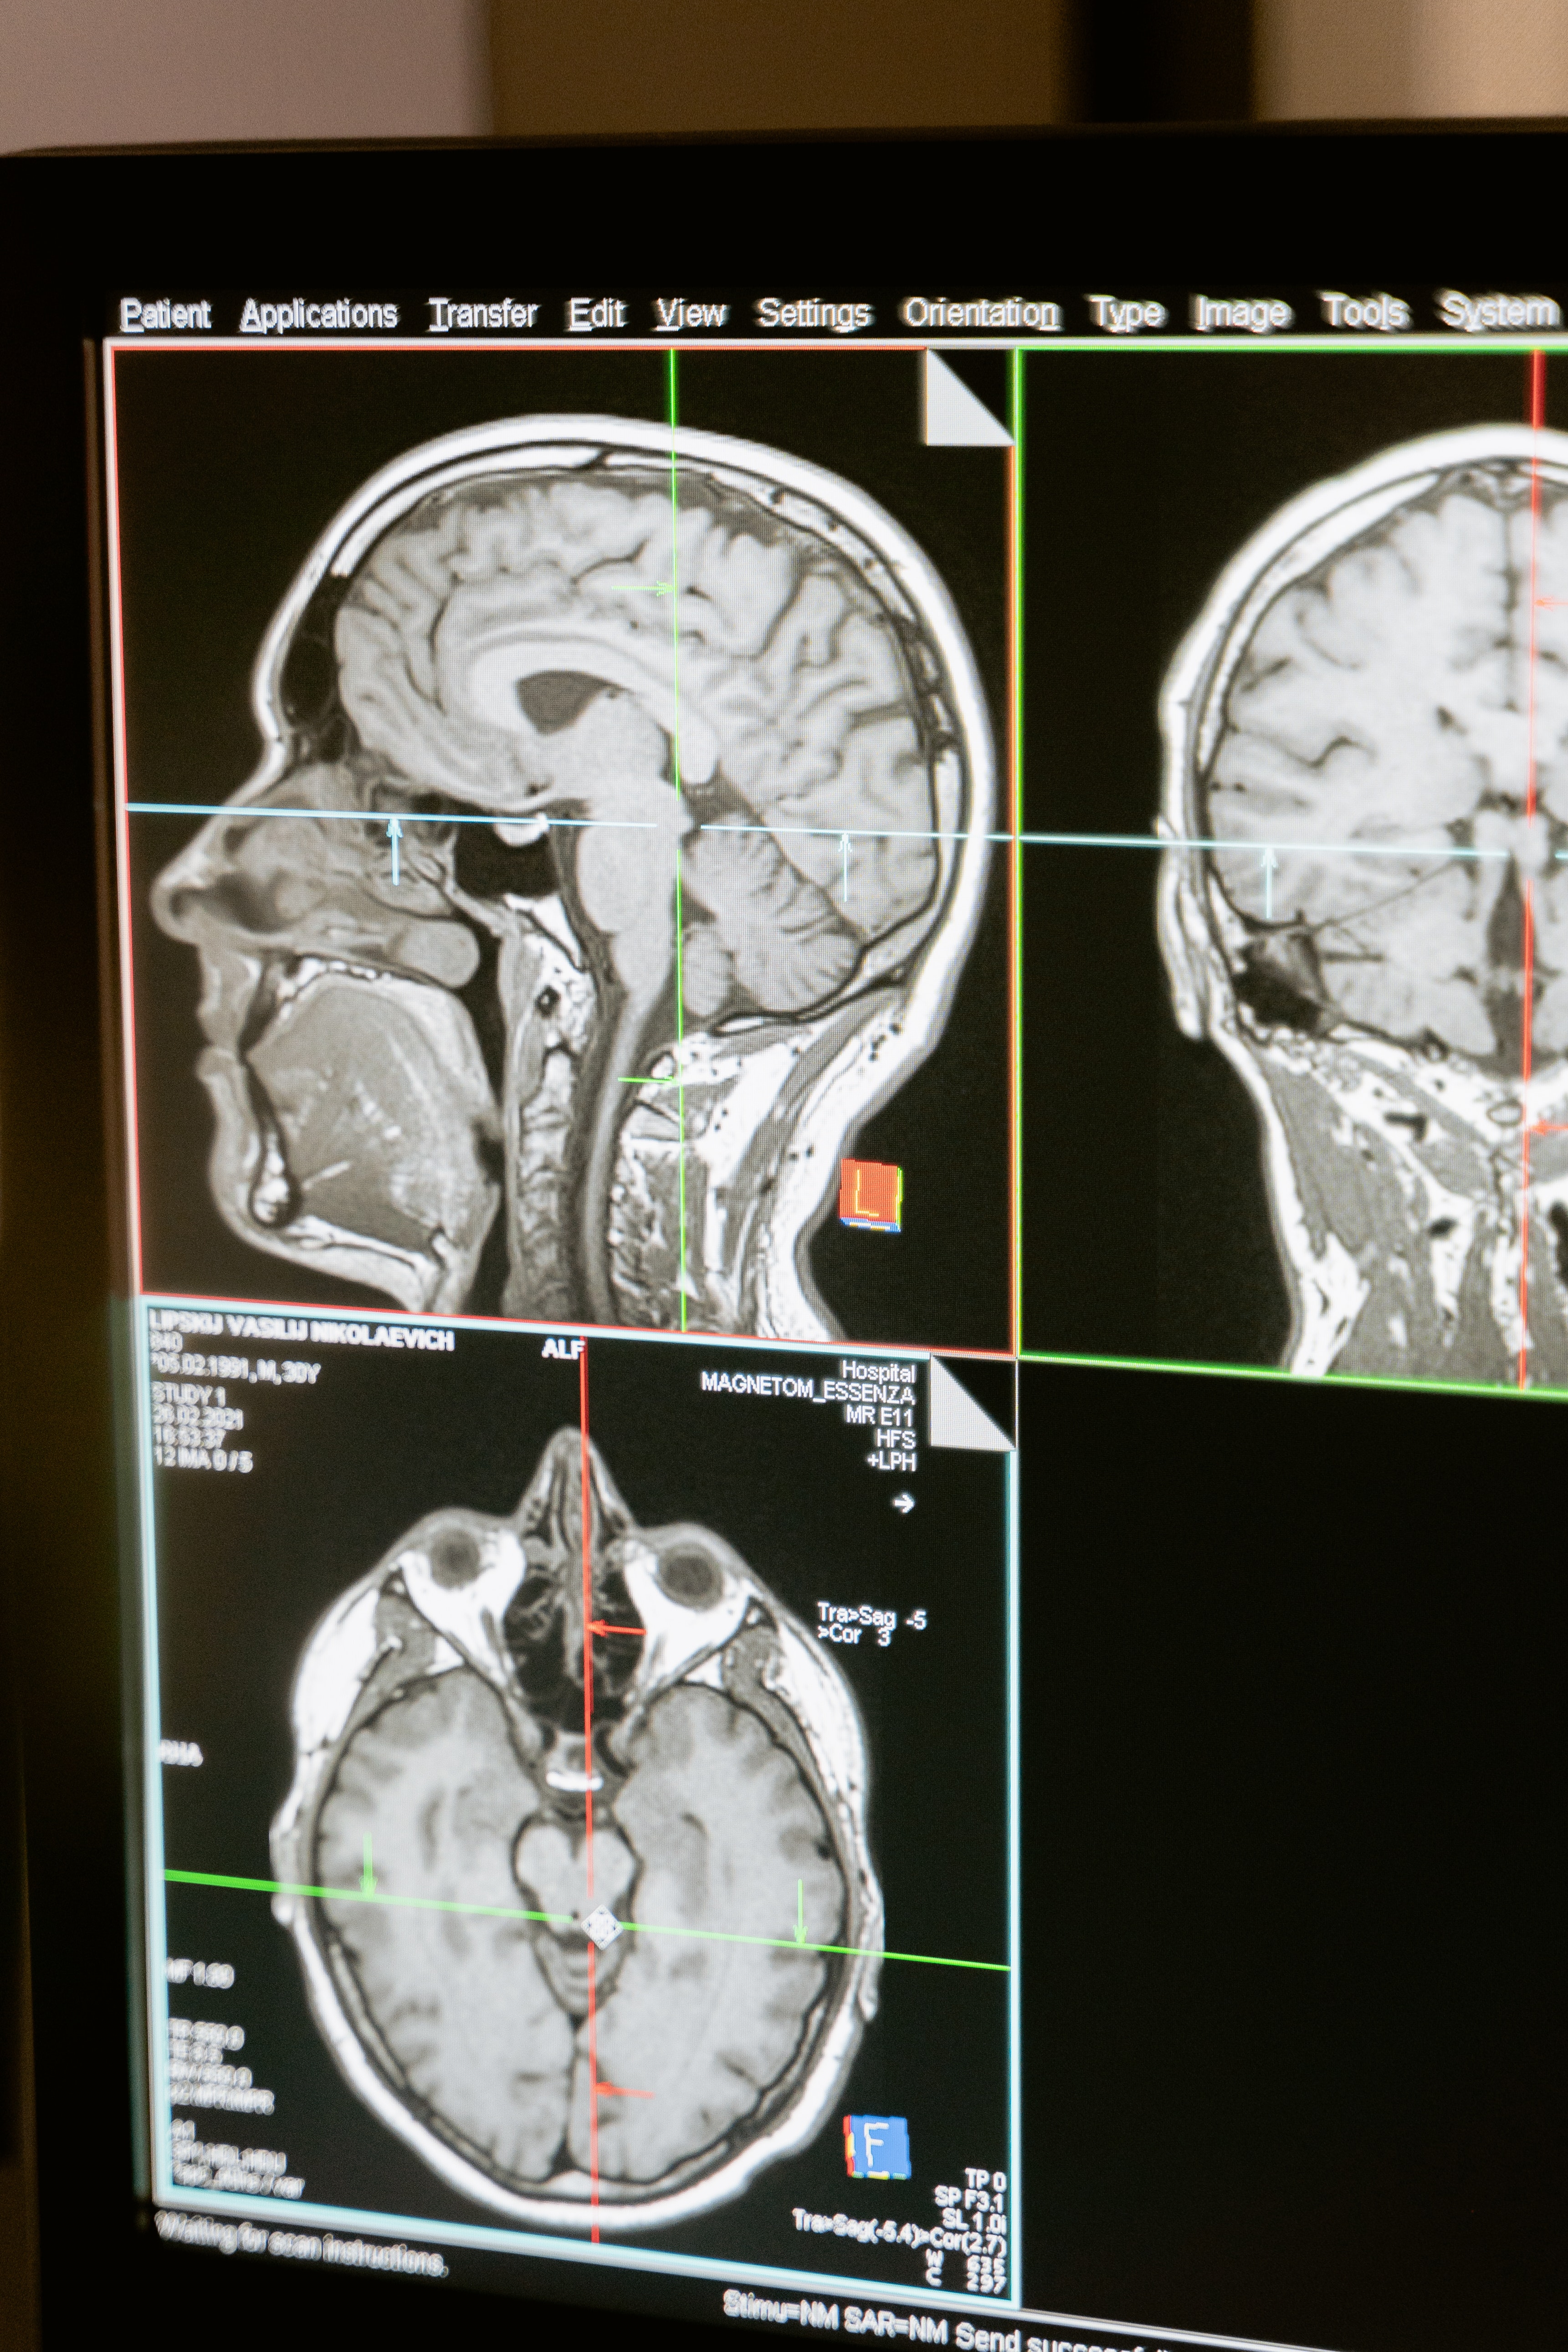

Le deuxième projet faisant intervenir l’IA en amont du traitement concerne la planification de celui- ci et le calcul des doses grâce à l’IRM. Le scanner est actuellement l’examen de référence pour la définition des volumes à traiter et des tissus sains à épargner, mais aussi pour le calcul des doses de radiothérapie. L'imagerie par résonance magnétique (IRM) permet une meilleure visualisation et caractérisation des tissus mous entrainant une délinéation plus précise des tumeurs et tissus sains. « Cet examen non irradiant sera aussi demain l’outil de référence pour le calcul des doses. Une imagerie par résonance magnétique peut en effet être utilisée pour générer ce que l’on appelle un « pseudo-CT » sur lequel le calcul de dose sera effectué. Cette idée n’est pas nouvelle, mais les techniques d’intelligence artificielle laissent entrevoir un gain substantiel de précision et un gain de temps considérable dans cette étape », précise le Pr Vincent Grégoire, chef du Département d’Oncologie Radiothérapique du CLB, radiothérapeute spécialiste mondial des tumeurs de la tête et du cou.